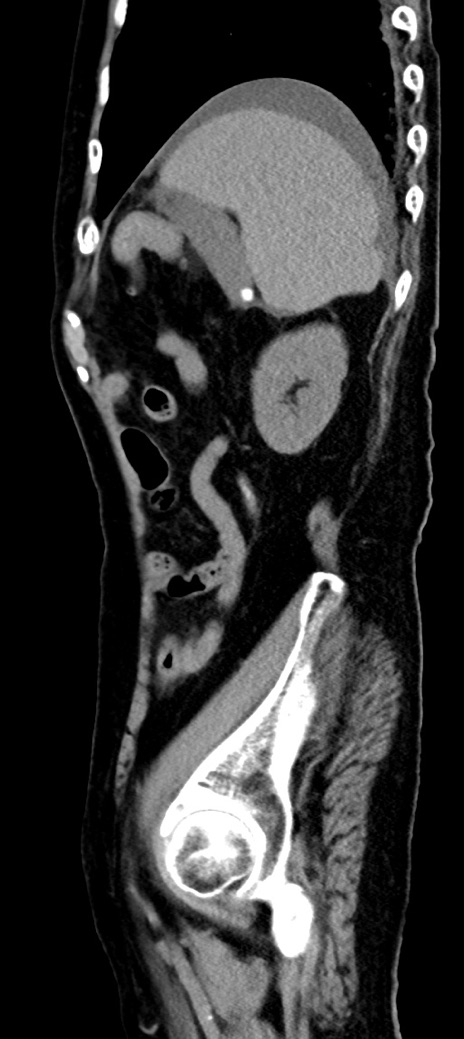

冠状断像

他院CT